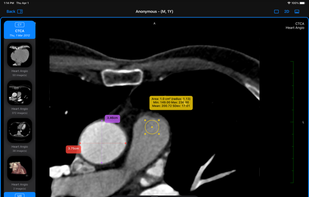

Falcon offers Many apps for different OS Than one for iPhone & iPad is called Falcon Mx™ And it’s is not CE or FDA-cleared and SHOULD NOT be used for primary diagnosis. While that of Mac is Called Falcon MD™ and it’s FDA-Cleared